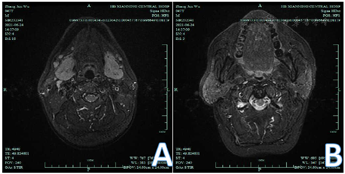

入院后完善相关检查:血液分析(五分类):嗜酸性粒细胞(#) 0.69×109/L↑;嗜酸性粒细胞(%) 13.00%↑;红细胞4.28×1012/L ↓;血红蛋白129.0 g/L ↓;红细胞压积37.6%↓;肝肾功能:尿酸477 umol/L ↑;白蛋白36.0 g/L ↓;球蛋白44.7 g/L ↑;白球比0.8 ↓。凝血功能五项、尿分析+尿沉渣定量、粪便常规+潜血+寄生虫未见异常。甲功五项、男性肿瘤标志物:未见异常,感染性疾病筛查(输血科):乙肝病毒表面抗体30.62 mIU/ml ↑;免疫球蛋白+补体定量测定:免疫球蛋白G 2040.2 mg/dl ↑,自身免疫抗体全套2(ANA核型、ANA定量、ENA谱):阴性。颌下腺MR平扫诊断内容:1.左侧腋窝淋巴结肿大;2.双侧颌下区、颈部小淋巴结显影。头颅MRI平扫诊断内容:颅脑MRI扫描未见明显异常。CT-平扫全腹诊断内容:胆囊切除术后改变。CT-平扫胸部及心脏诊断内容:右肺上叶少许炎症。免疫球蛋白G4 53.6 g/L↑,考虑IgG4相关性疾病,至华中科技大学同济医学院附属同济医院就诊,磁共振-眼眶平扫:双侧泪腺肿胀;冠状位TW1扫描所及双侧腮腺体积增大;双侧筛窦和额窦炎。再次重新阅读我院头颅MRI(图1)及颌下腺MRI (图2A、B)可发现患者泪腺、腮腺及颌下腺均肿大。于华中科技大学同济医学院附属同济医院口腔科行左侧颌下腺切除,病检结果:灰红不整涎腺组织4.6 cm×3 cm×2 cm,临床已部分切开,切面灰红分页状,未见明确实性肿块,病理诊断:(左颌下肿物)镜下见涎腺小叶被增生的纤维结缔组织分隔,小叶内外可见浆细胞为主的慢性炎性细胞浸润,淋巴滤泡增生,免疫组化结果提示IgG阳性细胞数热点区约100个/HPF,且IgG4/IgG大于40%,考虑IgG4相关性疾病可能性大。免疫组化:浆细胞IgG4热点区约150个/HPF,且IgG4/IgG大于40%,CD19(+),κ和λ(部分阳性,无限制性轻链表达),淋巴滤泡CD20(+,阳性对照+),CD21(FDC网+),ki-67(生发中心高,滤泡间区散在+);滤泡间区CD3(散在+)(图3A、B)。

本例男性患者以双侧眼睑浮肿为首发症状,就诊于眼科,未能明确诊断,4个月后开始出现左侧聂顶部头痛以及双侧颌下腺肿大,门诊查肝肾功能提示白蛋白下降、球蛋白升高,以肝功能异常收入消化科。入院后排除肝源性、肾源性及心源性病因,甲功五项正常排除甲状腺相关性眼病,嗜酸性粒细胞、免疫球蛋白G升高,请口腔科、神经内科会诊,均未考虑到IgG4-RD。因双侧颌下腺肿胀拟转口腔科行手术治疗,经上级医院口腔科教授会诊,最终明确诊断为IgG4-RD,避免了不必要的手术治疗。IgG4-RD可以累及到多个脏器,当累及到眶周及眶内组织时,为IgG4相关性眼病,发生率约3.6%~12.5%[9]。IgG4相关性眼病是一种慢性系统性疾病,泪腺、眼外肌和眶下神经常常受累,常常为全身病变的首发症状。眼科医师对该疾病缺乏足够的认识,患者常常因泪腺肿大或眼外肌肥大,经常误诊为炎性假瘤、甲状腺相关眼病等眼眶疾病而延误治疗。眼眶IgG4相关疾病患者常表现为长期无痛性眼眶肿胀、眼球突出,视力损害不明显,结膜一般不受累,可伴有外周淋巴结肿大。但有个别患者会出现复视、视力下降、眶周疼痛等症状。影像学检查可发现眶内弥漫性或局灶性肿大的病灶,与周围正常组织形成鲜明对比,可累及眼眶、泪腺、眼外肌、球后软组织、眶下神经、视神经,巩膜,其中以双侧泪腺受累最为多见。眼眶IgG4相关疾病的诊断需结合患者临床表现、实验室检查、影像学检查及病理组织学检查。本例患者已确诊为IgG4-RD,双侧眼睑浮肿、左侧头痛,合并泪腺肿胀,经激素联合免疫抑制剂治疗后症状缓解,眼眶IgG4相关疾病亦可明确。因影像科医师对IgG4-RD认识不足,阅片时未能发现泪腺、颌下腺及腮腺肿胀,且患者以眼睑肿胀、头痛为主要表现,眶周疼痛在临床较少见,眼科医师对该病认识亦不足,导致未能及时诊断该病。米库利奇病(MD),其特征是双侧对称性泪腺、腮腺、颌下腺无痛性持续肿大[10],血清IgG4浓度升高,IgG4+浆细胞浸润到腺体组织。MD也称为IgG4相关性泪腺炎和涎腺炎,所以该患者亦可诊断为米库利奇病。